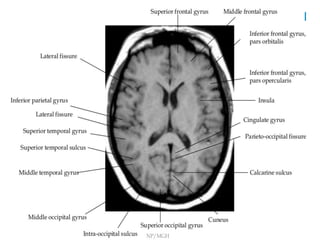

-Occipital lobe is divided by calcarine sulcus into

lingual and cuneus gyrus

Occipito-parietal	sulcus	on	axial	image

-Deepest	sulci	posteriorly	perpendicular	to	interhemispheric	fissure

-Supramarginal gyrus lies at end of sylvian fissure

-Angular gyrus lies ventral to supramarginal gyrus

-Medial surface of parietal lobe is precuneus which lie immediately

rostral to parieto-occipital sulcus